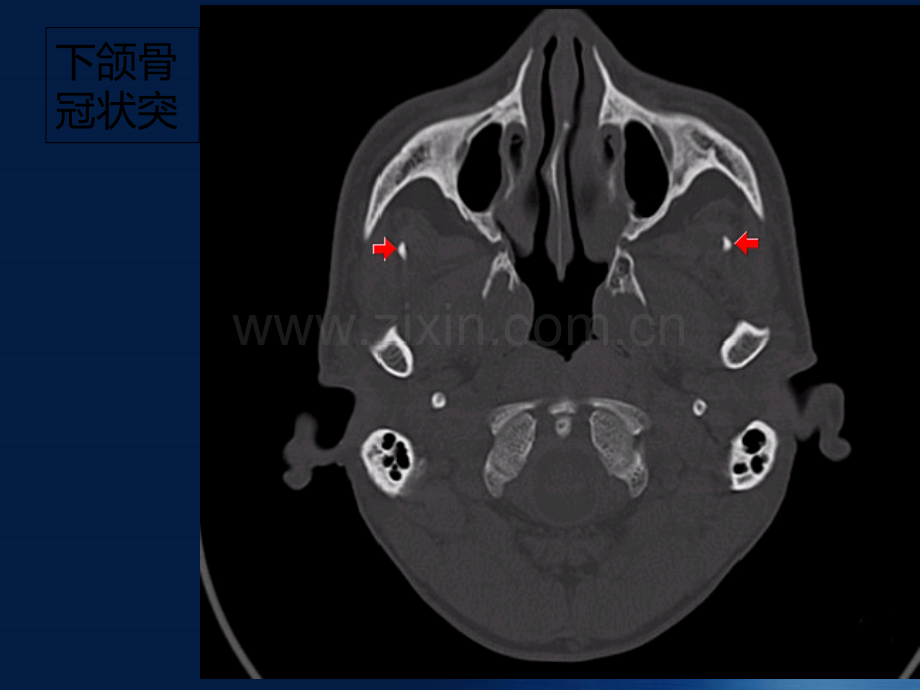

颅底骨质解剖下颌骨冠状突下颌颈乳突枕髁翼上颌裂翼腭窝蝶腭孔翼板翼突茎突茎突基底部下颌骨髁枕骨(髁、基底部)枕骨鳞部枕乳缝蝶骨体左蝶骨蝶骨大翼蝶骨嵴蝶骨嵴蝶骨大翼颧骨颧弓关节结节(颧弓前根部)斜坡(枕部)颧面孔脊孔舌下神经管舌下神经穿行眶下裂蝶鳞缝鼓乳突裂颈动脉管外口卵圆孔三叉神经第三支下颌神经经卵圆孔、眶上裂破裂孔脊孔颈静脉孔1、舌咽神经2、迷走神经3、副神经岩枕裂岩蝶裂翼管蝶鳞缝颞骨岩部颞骨鳞部颞骨鼓部资料整理仅供参考,用药方面谨遵医嘱